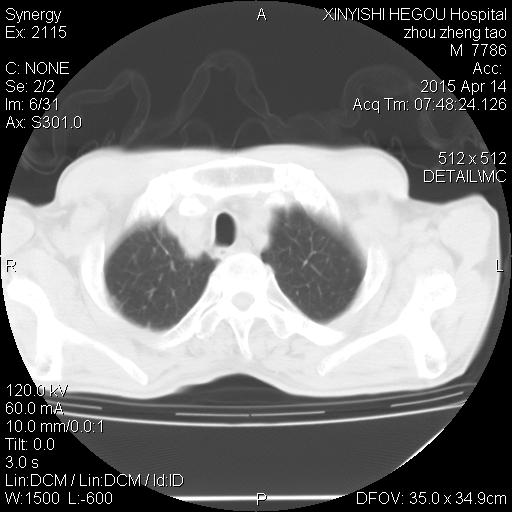

CT50271:男,65岁,咳嗽一周

右中叶支气管闭塞,局部疑似有肿块,中叶肺不张,考虑中央型肺癌,增强有意义。支持!还需除外支气管内膜结核。

中叶肺不张,考虑中央型肺癌,建议支气管镜检查。

右中叶肺不张,建议增强排除占位病变!

右中叶支气管闭塞,局部疑似有肿块,中叶肺不张,考虑中央型肺癌,增强有意义。